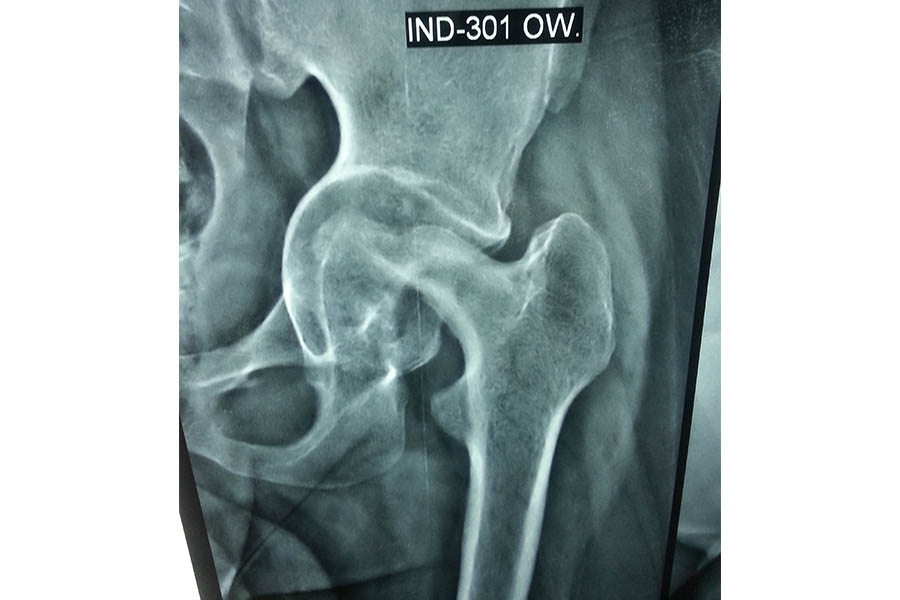

Total Hip Replacement

Difficult Replacement

Case 1